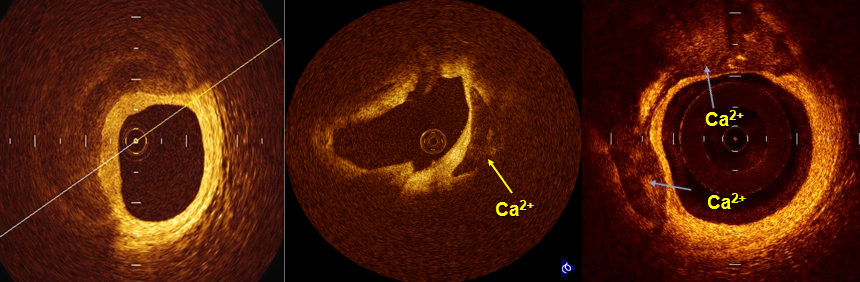

OCT图像上的斑块类型可分为三类:纤维斑块、脂质斑块、钙化斑块,如图5。

图5

③ 钙化斑块(Calcified Plaque,图8)

图8 边界清晰,低反射,低衰减,不均一的低信号区